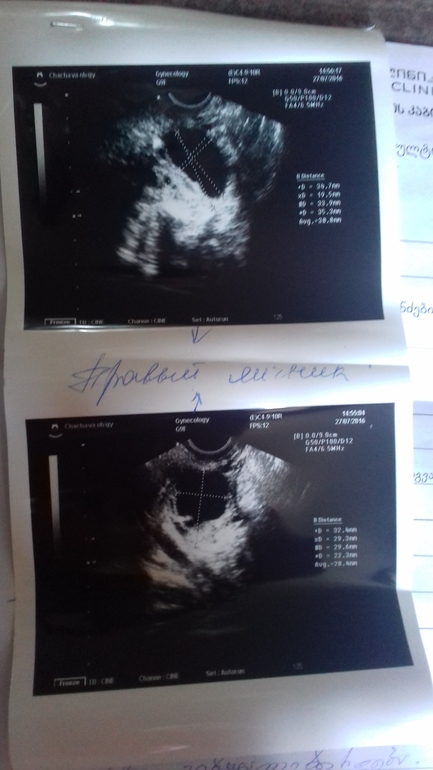

Девочки,всем привет)Этот цикл у меня начался с задержки 8-9 дней, из-за дюфастона.Моя врач сказала на 5 дц сделать узи, посмотреть,как там обстоят дела,но я уехала в Тбилиси,и пошла на узи тут...сегодня 6 дц,на узи нашли доминантный фоллик 28 мм, он же под вопросом похож на фолликулярную кисту. А я понять не могу, откуда киста может взяться, если в прошлом цикле мне специально стимулировали О,чтоб избежать этой кисты. Здесь мне объяснить толком ничего не могут,врачи разговаривают на ломаном русском, результаты отправила своей Г по вотс апу, но она тоже ничего не объяснила,сказала с 11 по 25 дц начать пить дюф, и на 21 дц к ней прийти. Помогите разобраться, киста это или нет?

p.s. Неожиданно для меня,сегодня почти сразу после узи появились признаки О (выделения,шейка матки, покалывание в яичнике).Тест на О тоже положительный (фото прилагается).И всё это на 6 дц!!!